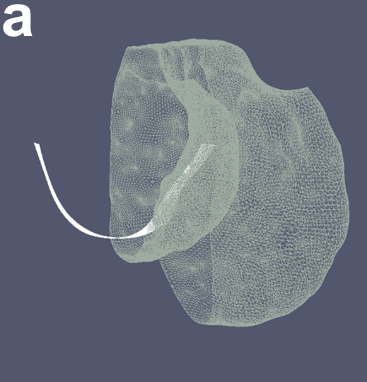

Along with the proposed learning-based cost functions, it is beneficial to leverage the contextual information from multiple time-points to improve the overall segmentation accuracy. Sequential yearly follow-up MRIs of the same knee provide spatial and temporal contextual information which helps to reduce the inter-time-point variability while ensuring physiologically feasible losses of cartilage during osteoarthritis progression. The crucial first step in 4D segmentation is to register the pre-segmented mesh surfaces and the respective images across time-points to establish correspondences temporally between the similar regions of the knee in 4D. A rigid registration was used given that only slight changes in bone shape occur with disease progression. The same configuration is maintained across all time-points in terms of the geometric graph parameters and topology. Enforcing contextual information temporally is done by linking adjacent time-points using inter-time-point edges in the underlying 4D LOGISMOS graph.

III-A Establishing Temporal Correspondences

After pre-segmentation of each of the time-points, iterative closest points (ICP) algorithm was used to register the pre-segmented mesh surfaces. With a large translational or rotational movement between the two-time-points, there is a tendency to mismatch the surfaces, i.e., femur matched to the tibia or vice versa if they were the closest in terms of the least squares optimization. To prevent the mismatch, a two step registration was employed. The first step used the femur mesh only for ICP registration. This transform matrix was applied on both the femur and tibia meshes. After the first transform ensured that femoral and tibial surfaces were reasonably aligned, the ICP registration was run again using both the femur and tibia points together as a unified point cloud to further refine the registration. This ensured that vertex to vertex correspondences and thereby column correspondences were established. Fig. 3 illustrates the establishment of correspondence between two time-points. The same two-step transformation matrices were applied to the entire images.